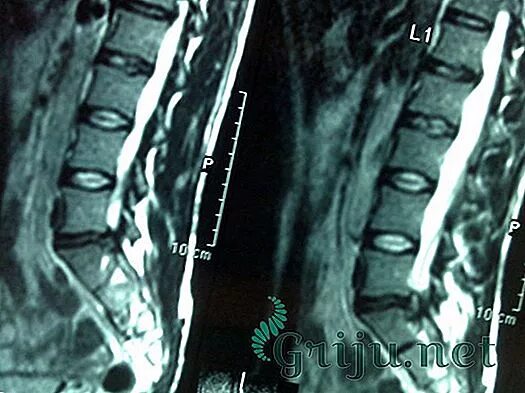

Операция по удалению грыжи шейного отдела